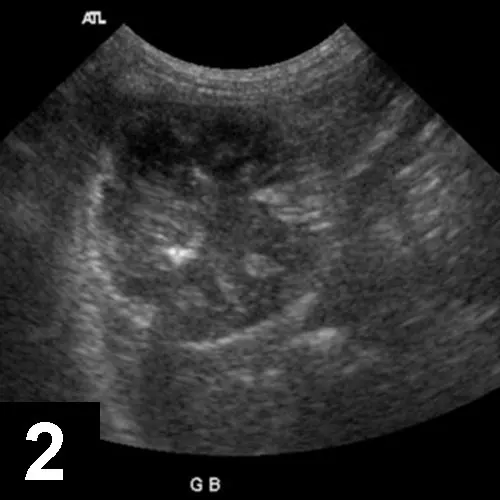

Figure 1B

In this ultrasound, the gallbladder contents show a narrow hypoechoic region at the periphery with central heterogeneous material filling most of the gallbladder lumen. The irregular hypoechoic areas within the heterogeneous material correspond to areas within the bile accretion with a higher mucus content admixed with areas of echogenic bile. The gallbladder contents were immobile when the patient was repositioned.